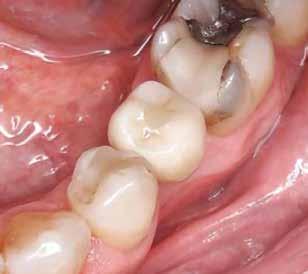

1. ábra: A műtét előtti szituáció, megfigyelhető az implantátumok közötti konkáv terület, ahova könnyen beragad az ételmaradék, és könnyen kialakul a periimplantitis.

Egy 47 éves páciens jelentkezett nálunk egy alsó, hátsó foghiánnyal, ahol jelentős csontfelszívódást tapasztaltunk a moláris fogak korábbi eltávolítása miatt (1. ábra). Két implantátum körül is volt ínyrecesszió, illetve a keratinizált íny mennyisége minimális volt (kevesebb, mint 1 mm). 4 hónappal az implantációt követően ínykorrekciót végeztünk.

2–5. ábra: A metszések és a deepitelizáció. – 6–9. ábra: Félvastag lebeny. – 10. ábra: A nyelezett ínylebeny „bepróbálása”.

horizontális metszéssel kötöttük össze (2–5. ábra). A metszések hosszát és a köztük lévő távolságot minden esetben a lágyszövet augmentációhoz szükséges keratinizált szövet határozza meg. A lebeny deepitelizációját egy 15C-s szikepengével végeztük (6. ábra). Ezt követően félvastag lebenyt preparáltunk (7. ábra). A lebenyt apikálisan, az alapjáról belső, felületes metszéssel felszabadítottuk, hogy passzívan áthelyezhessük és rögzíthessük, feszülés nélkül. Meziális irányba 180 fokkal átforgattuk (8–9. ábra). A meziális papillát alagúttechnikával (tunnelling technique) készítettük elő a graft befogadására (10. ábra). Az így kialakított lebenyt a recipiens ágyban rögzítettük az újonnan kialakított vesztibulum alapjánál 5-0 nem felszívódó PTFE (Coreflon, IMPLACORE) varratokkal. A graftot behajtottuk az ínyszél alá és meziális oldalon rögzítettük PTFE varratokkal (11–14. ábra)